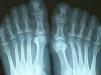

55 year old woman who complains of polyarticular joint pain, predominantly in the hands. The pain was diffuse, continuous and low in intensity. The physical examination revealed diffuse thickening of soft tissues of hands and feet (Figs. 1 and 2).

Radiographs of hands and feet (Figs. 3 and 4) showed an increase of soft tissue and joint space. In addition, the patient underwent laboratory analyses. We found serum growth hormone (GH) and IGF-1 were elevated: 5.67g/l (0–3.5g/l) and 121nmol/l (6.1–24, 8nmol/l), respectively. The patient was diagnosed with acromegaly. To complete the study she underwent a skull X-ray (Fig. 5) which featured an enlarged sella and a brain MRI detected the presence of a pituitary adenoma (Fig. 6).

Radiologically, at an early stage, there is increased joint space due to hyaline cartilage hypertrophy that later evolves to a pattern indistinguishable from primary osteoarthritis.3